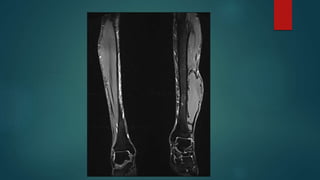

• #103 Synovial sarcomas are relatively common intermediate-to-high grade malignant soft tissue tumours, often with an initial indolent course, affecting young patients, and most commonly involving the soft tissue surrounding the knees